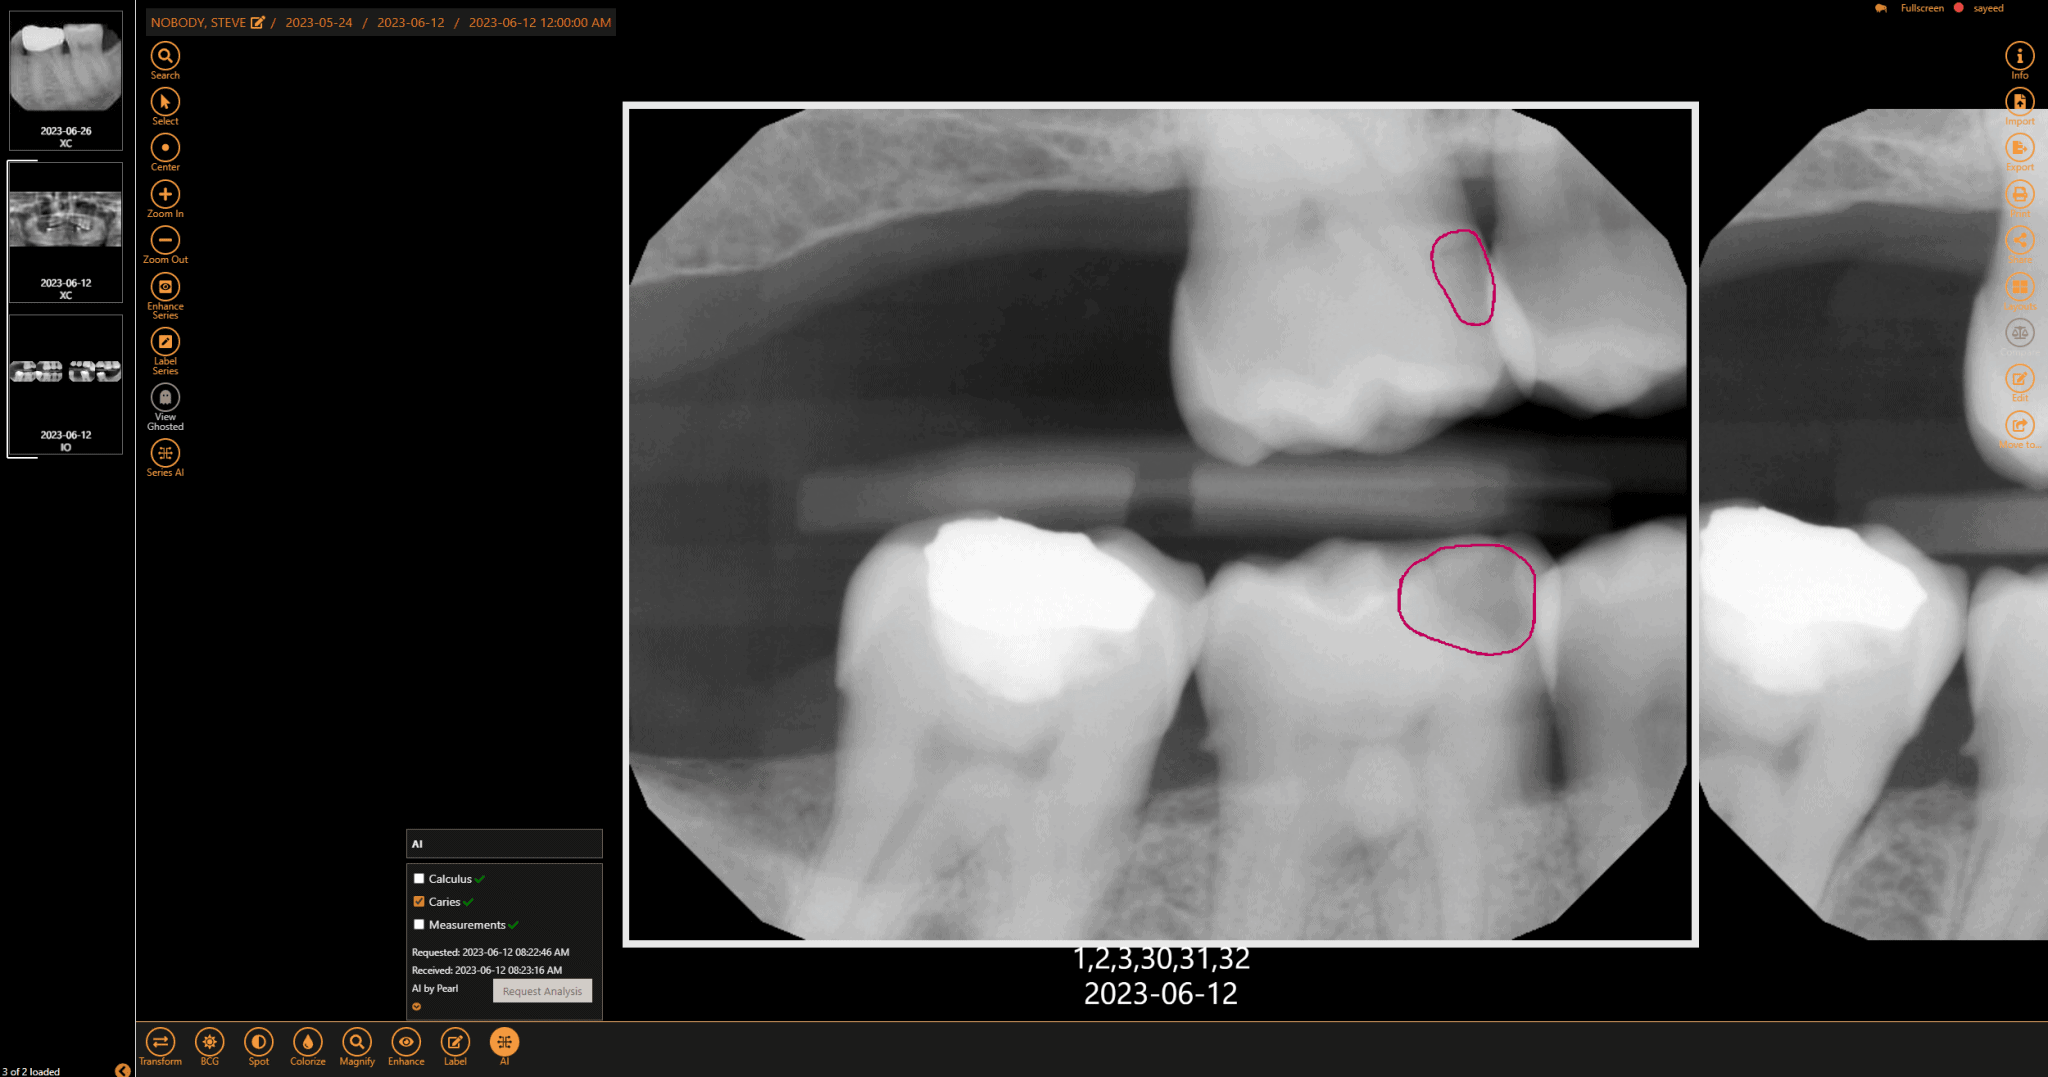

Dental radiology is a specialized field of medical imaging that focuses on the use of X-rays and other imaging modalities to diagnose and treat dental and oral health conditions. Radiologic technologists and dental hygienists play a crucial role in this field, working closely with dentists and other healthcare professionals to provide high-quality imaging services.